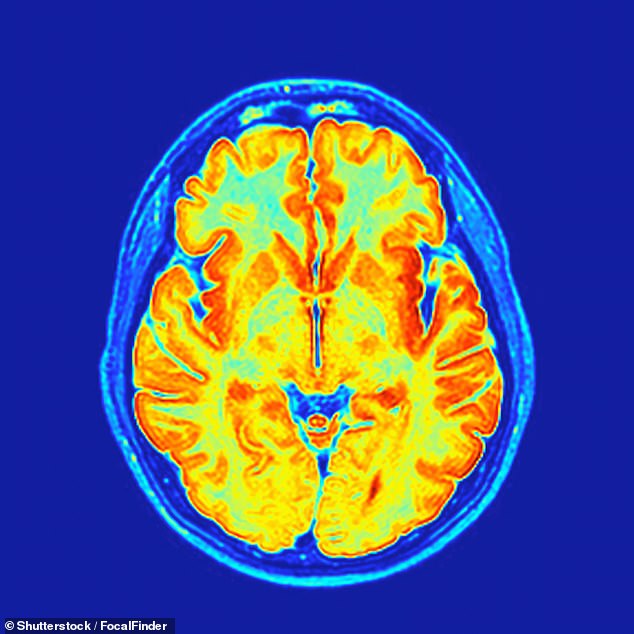

The research, led by Professor Susana Carmona of the Gregorio Marañón Health Research Institute, tracked 127 women through a series of MRI scans and hormone tests before, during, and after pregnancy. The results painted a striking picture of transformation. On average, expectant mothers lost nearly five percent of their grey matter—the tissue responsible for processing emotions, information, and empathy. This finding challenges the common narrative that pregnancy causes intellectual decline, instead suggesting a deliberate and adaptive rewiring of the brain.

'Grey matter loss isn't a sign of decline,' explained Professor Carmona. 'It's akin to pruning a tree. Some branches are cut to make it grow more efficiently.' The study revealed that while grey matter partially returned within six months postpartum, the initial shift indicated the brain was 'priming' itself for the heightened emotional and cognitive demands of motherhood. This rewiring, driven by hormonal fluctuations and changes to blood vessel networks, appears to be a natural process rather than a deficit.